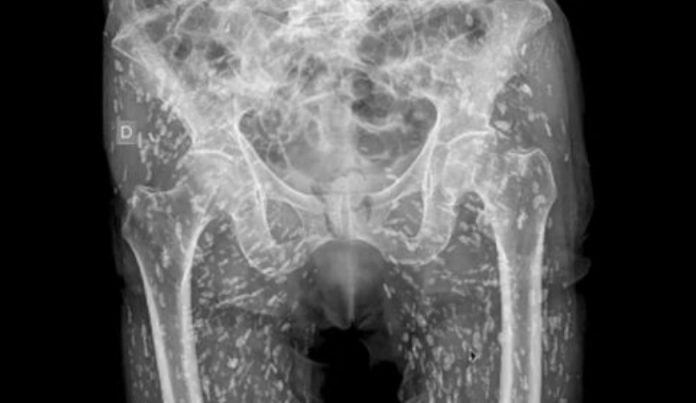

ഇന്നുവരെ കണ്ടതില്‍ ഏറ്റവും ‘ഭയാനകമായ എക്‌സറേ ദൃശ്യങ്ങള്‍’ എന്നാണ് ഡോ. സാം എക്സിൽ കുറിച്ചത്. ശരിക്ക് പാകം ചെയ്യാതെ പന്നിയിറച്ചി കഴിച്ചതിലൂടെ യുവാവിന്റെ ശരീരത്തിനുള്ളിലെത്തിപ്പെട്ട നാടവിര മുട്ടയിട്ട് പെരുകിയ ദൃശ്യങ്ങളായിരുന്നു എക്സ്റേയിൽ ഉണ്ടായിരുന്നത്.

ഏത് സാഹചര്യത്തിലായാലും ശരിയായി വേവിക്കാതെ പന്നിയിറച്ചി കഴിക്കുന്നത് അപകടകരമാണെന്ന മുന്നറിയിപ്പ് കൂടിയാണ് ഡോ. സാം ഈ പോസ്റ്റിലൂടെ നൽകുന്നത്. വേദന സഹിക്കാൻ വയ്യാതെ ആശുപത്രിയിലെത്തിയ യുവാവിന്റെ ശരീരത്തിനുള്ളിൽ ഇടുപ്പിലും കൈകാലുകളിലുമായി നാടവിരകളുടെ നൂറുകണക്കിന് മുട്ടകളാണ് കണ്ടെത്തിയത്.

‘നാടവിരകളുടെ മുട്ടകൾ യുവാവിന്റെ ശരീരത്തിനുള്ളിൽ ഏകദേശം എല്ലായിടത്തുമുണ്ടായിരുന്നു. അവ എണ്ണാനാവാത്ത വിധം പെരുകിപ്പോയിരുന്നു.  ശരീരത്തില്‍ എവിടേക്ക് വേണമെങ്കിലും ഇവയ്ക്ക് സഞ്ചരിക്കാനാവും. ഈ യുവാവിന്റെ  ഇടുപ്പുകളുടെയും കാലിന്റെയും  ഭാഗത്താണ് അവ  കൂടുതലായി അടിഞ്ഞുകൂടിയിരിക്കുന്നത്. – സാം  കുറിച്ചു.

ഈ അവസ്ഥയെ ടെനിയ സോലിയം ഇന്‍ഫെക്ഷന്‍ എന്നാണ് അറിയപ്പെടുന്നത്. ഈ അപകടകരമായ അണുബാധ നാഡീവ്യൂഹത്തെയോ തലച്ചോറിനെയോ  ബാധിച്ചാല്‍ രോഗിയുടെ നില അപകടാവസ്ഥയിലാവും.യുവാവിനെ പ്രാഥമികമായി പരിശോധന നടത്തിയപ്പോൾ എന്താണ് ഇടുപ്പ് വേദനയുടെ കാരണമെന്ന് കണ്ടെത്താന്‍ ഡോക്ടർ‌ക്ക് കഴിഞ്ഞിരുന്നില്ല. അങ്ങനെയാണ് എക്‌സ്‌റേ വഴി കാരണം കണ്ടെത്തിയത്.പോര്‍ച്ചുഗൽ സാവോ ജോവോ യൂണിവേഴ്‌സിറ്റ് ആശുപത്രിയിലെ ഡോക്ടർമാരാണ് യുവാവിന്റെ ഈ അവസ്ഥയെപ്പറ്റി കൂടുതൽ പഠനങ്ങൾ നടത്തിയതെന്ന് ഡോ. സാം കുറിച്ചു.  യുവാവ് ആദ്യം ചികിത്സ തേടിയത് 2021ലായിരുന്നു.